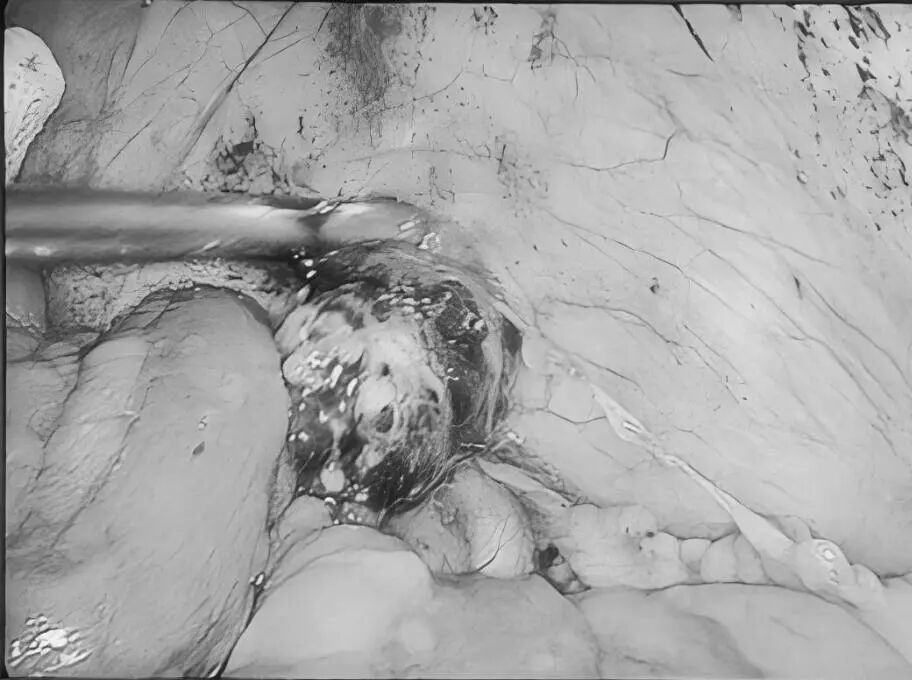

3月5日,贵州航天医院第51次晨读会由我院普外科主任、主任医师梁跃作学术交流,他以“腹腔镜下清扫No.253淋巴结的解剖问题”为题,全面讲解了No.253淋巴结的定义、清扫指征、清扫范围、相关解剖学知识等具体情况,并结合实际案例与图文对相关解剖进行了详细剖析,形象地展示了该区域复杂的解剖结构及在手术过程中可能遇到的解剖难点与要点。 普外科专家简介 梁 跃 普外科主任 主任医师 临床擅长:对普外科各类肿瘤手术具有丰富的临床经验。 毕业于遵义医学院,遵义市医学会小儿外科学分会常务委员,遵义市肛肠协会理事,遵义市医学会核医学分会(第二届)委员会委员;荣获第三期“黔医人才计划”优秀学员称号;主持市级课题1项,完成省级课题1项,在国内各类刊物上发表论文10余篇。 钱科洪 普外科 副主任医师 临床擅长:从事普外科临床工作30余年,对各类普外科疾病的诊治、乳腺、甲状腺、胃十二指肠、结直肠等疾病及疑难杂症具有丰富的临床诊疗经验。 毕业于遵义医学院临床医疗系,2009年前往中山大学附属第一医院微创外科进修学习,在国内各专业期刊发表论文数篇。 普外科简介 基本情况 贵州航天医院普外科成立于1968年,前身属于航天部O61基地3417医院外一科,3417医院、3427医院合并后更名为普外科,下设胃肠外科、肛肠外科2个亚专业科室,是中国疝病专科联盟单位,贵州医科大学附属医院胃肠外科专科联盟单位。开放床位40张,配备医护人员21人。 专科特色 普外科致力于胃肠及肛肠疾病的外科临床诊治及科研,以腹腔镜微创外科技术为本,形成以快速康复治疗胃肿瘤、结直肠肿瘤、小肠肿瘤、直肠脱垂、肥胖病、急腹症、各类疝、痔、瘘等专科特色,同时注重胃肠疾病尤其是结直肠恶性肿瘤的基础研究和临床转化研究,总体诊断和治疗水平在区域同级医院居于领先水平。 开展手术:腹腔镜下胃癌根治术,腹腔镜下袖状胃切除术,腹腔镜下胃肠道间质瘤切除术,腹腔镜下结、直肠癌根治术,胃癌、结直肠癌的精准治疗,腹腔镜下小儿疝气、成人疝修补术,腹腔镜下阑尾手术,内痔的硬化注射治疗及痔疮的微创治疗:ATH、PPH、TST,直肠脱垂的各种手术治疗,难治性伤口VSD技术,鼻胃肠管、肠梗阻导管置入术,肛肠术后间歇性导尿技术,并引进了中医适宜技术,也为各种化疗患者提供输液港安装,提高患者就医体验。 腹腔镜下腹股沟疝无张力修补术 腹腔镜下腹股沟疝 无张力修补术 腹股沟疝里金斯坦 (Lichtenstein)手术 PPH微创术治疗环状混合痔 黏连性或炎性肠梗阻-肠梗阻导管 腹腔镜袖状胃切除 腹腔镜阑尾切除术 腹腔镜阑尾肿瘤切除术 腹腔镜下结肠癌根治术 诊疗范围 胃肿瘤、结直肠肿瘤、小肠肿瘤、肥胖症、各类急腹症、腹部外伤、腹壁疝、便秘、直肠脱垂、痔疮、肛瘘、肛裂等胃肠、肛肠外科疾病。 end